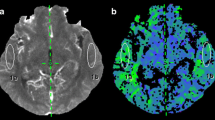

MR imaging protocol

Colour-coded ASL perfusion images with ROIs placed at predetermined places in the parietal and occipital regions. The first row represents preoperative images, and the second row represents postoperative ASL images. There was a significantly raised perfusion (more than 100% increase in CBF values) in the left parietal and occipital regions (yellow arrows). This case shows that the ASL changes can occur prior to parenchymal changes